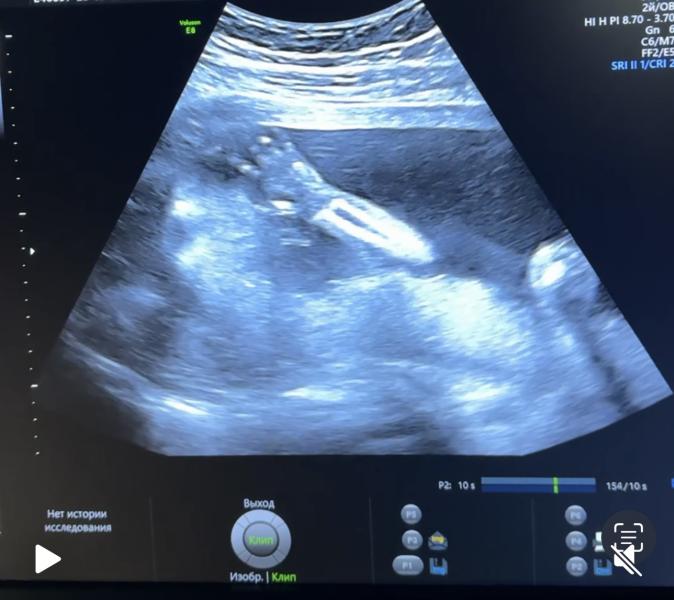

Второй скрининг: результаты и эмоции будущей мамы

Вчера был наш 2-ой скрининг 😌

Все отлично, весим 362 г. 🥹

Не захотел показаться в профиль, полюбуюсь на ручку 😁🥰